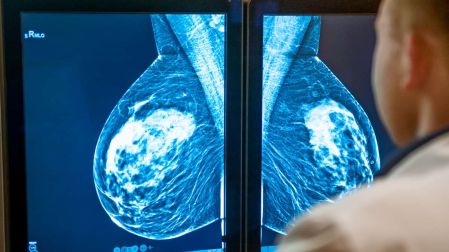

Finalmente, a partir de los 40 años y hasta los 69, todas las mujeres deben hacerse la mastografía. De acuerdo a la Dra. Kictzia Yigal Larios Cruz, jefa de radiología en FUCAM, “la mastografía es el único método que salva una vida”, pues puede detectar lesiones tan pequeñas como un grano de arroz.

La mastografía es el método más efectivo para detectar el cáncer de mama a tiempo. Desmiente los mitos y cuida tu salud.